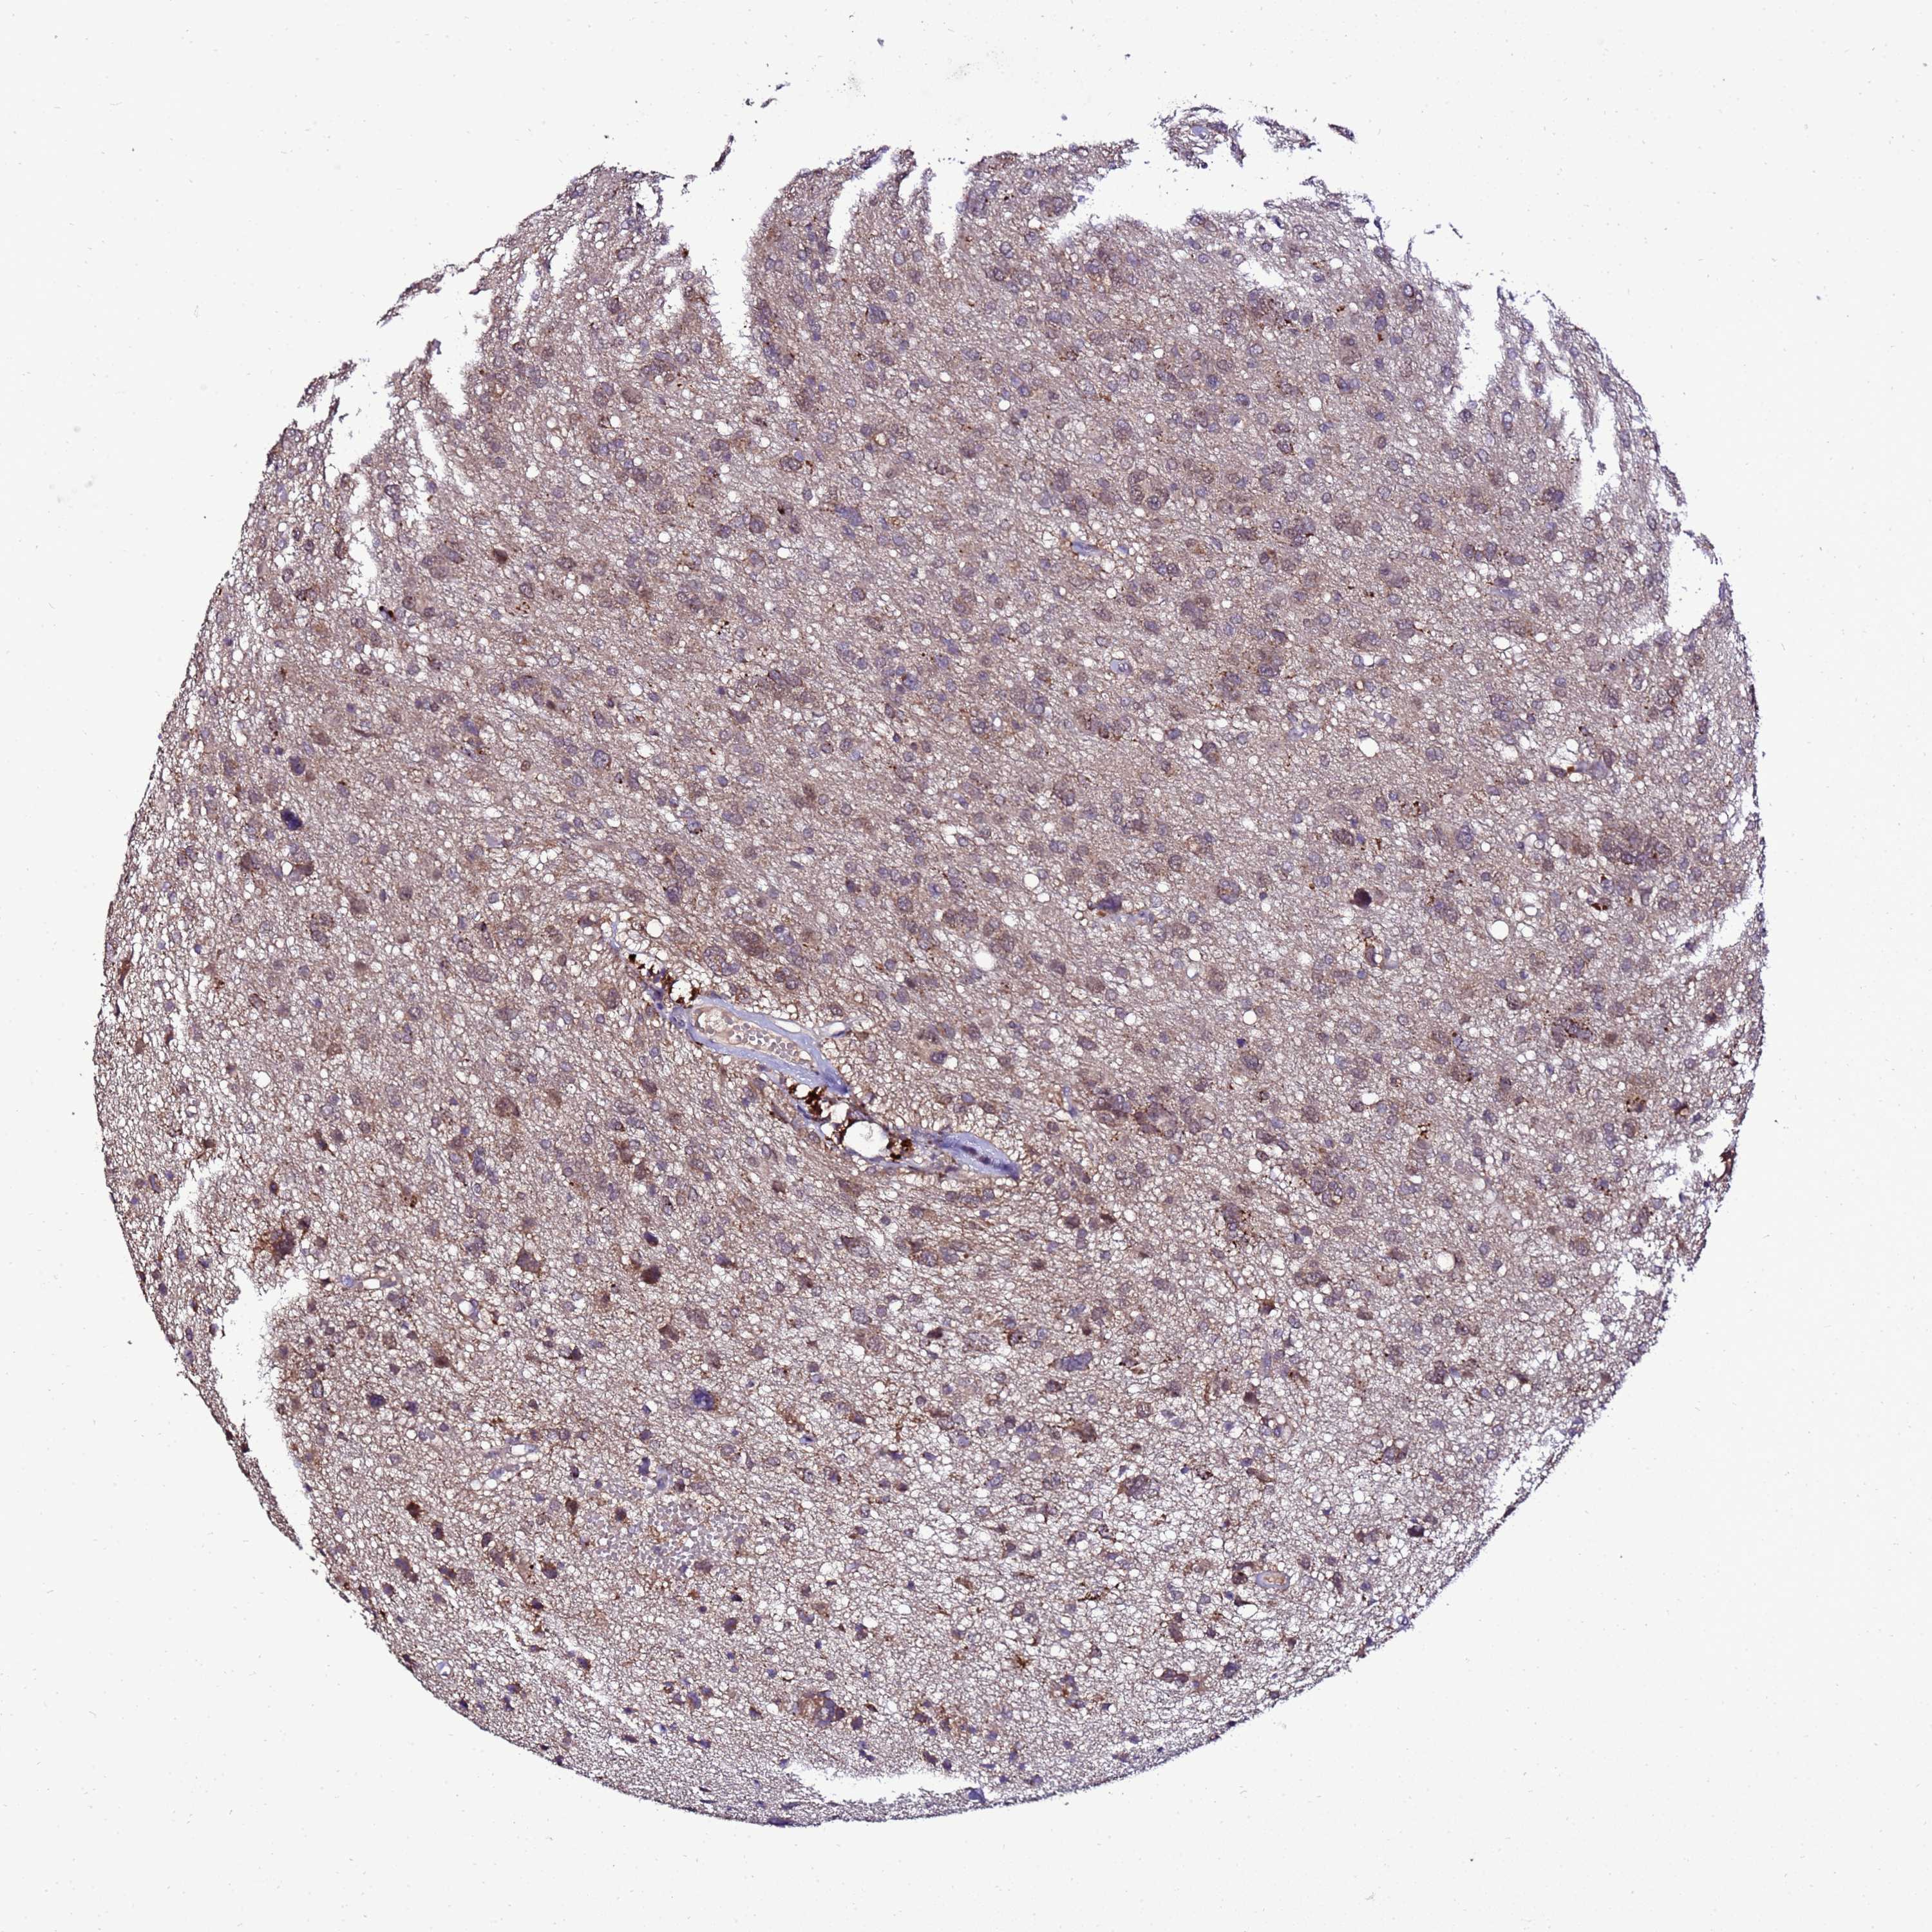

GLIOMA - Protein expressioni

A mouse-over function shows sample information and annotation data. Click on an image to view it in a full screen mode. Samples can be filtered based on level of antibody staining by selecting one or several of the following categories: high, medium, low and not detected. The assay and annotation is described here.

Note that samples used for immunohistochemistry by the Human Protein Atlas do not correspond to samples in the TCGA dataset.

Antibody stainingi

Antibody staining in the annotated cell types in the current human tissue is reported as not detected, low, medium, or high, based on conventional immunohistochemistry profiling in selected tissues. This score is based on the combination of the staining intensity and fraction of stained cells.

Each image is clickable and will lead to virtual microscopy that enables deeper exploration of all samples and also displays staining intensity scores, fraction scores and subcellular localization as well as patient and tissue information for each sample.

Antibody HPA044373

Staining

High

Medium

Low

Not detected

Intensity

Strong

Moderate

Weak

Negative

Quantity

>75%

75%-25%

<25%

None

Location

Nuclear

Cytoplasmic/membranous

Cytoplasmic/membranous,nuclear

Glioma, malignant, High grade

Glioma, malignant, Low grade

Glioblastoma, NOS